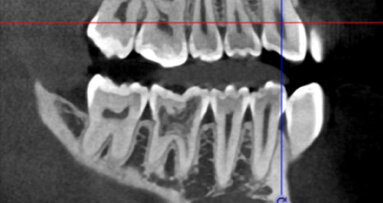

Úspěšné endodontické ošetření závisí na řadě faktorů, včetně správné instrumentace, úspěšné irigace a dekontaminace systému kořenových kanálků včetně apikálního zakončení a špatně přístupných oblastí jako jsou zúžení a postranní a vedlejší kanálky (obr. 1a, 1b).